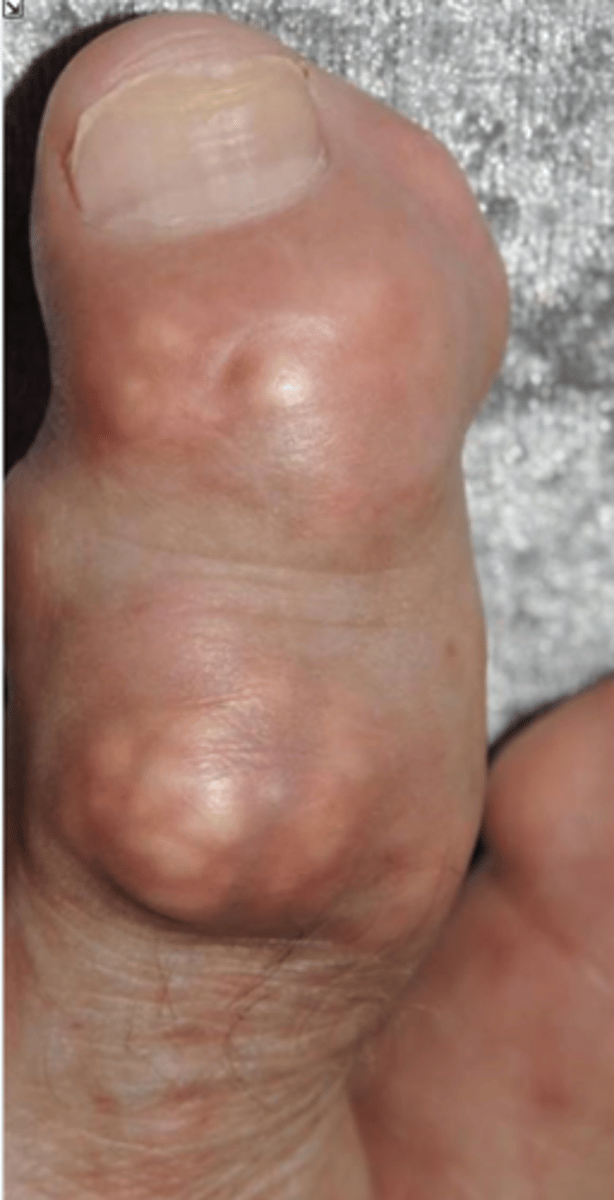

- Dense soft tissue tophi (swelling)

- Bone erosions

- Overhanging margin sign

- Secondary degeneration

- 1st MTP MC joint